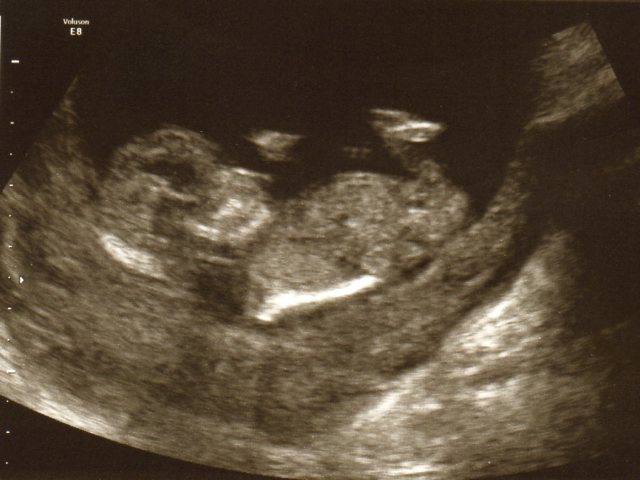

And 21 Weeks

Attachment 13127

Hi thanks for the reply. Yes in the 3rd picture (21 weeks) can't really tell also was wondering does it matter on the positioning of the baby? I mean if the baby is not horizontal and is at a bit of a vertical angle can it make a flat nub look pointing up?

I agree, looks like a lil boy from the 12 week shots, no gender seen in the 20 weeks!! Baby should be laying as flat as possible for a more accurate guess.

I agree the 12 week scan has a clear shot of a boy nub. I can't see anything on the 20 week scan. Potty shots are better on 20 week scans.